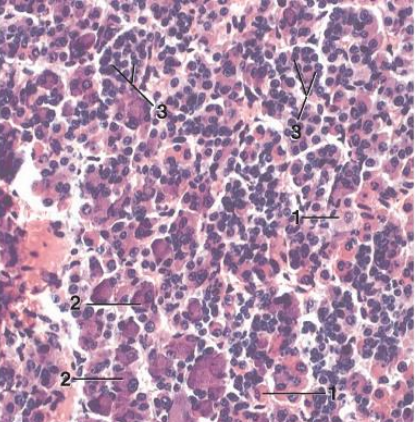

adenohypophysis pars distalis

Largest part of pituitary gland- many cell types

–Chromophils and Chromophobes

Chromophils (Acidophils and Basophils)

• Acidophils (1) Cells that contain the polypeptide hormones-will stain red or orange

• Somatotrophs

Growth hormone (GH)

somatotropin

• Lactotrophs

Prolactin (PRL)

Basophils in pars distalis of adenohypophysis of pituitary gland

• Basophils (2) Cells that contain the glycoprotein hormones-will stain bluish color

Thyrotrophs

Thyroid stimulating hormone (TSH)

Gonadotrophs

Follicle stimulating hormone (FSH)

Luteinizing hormone (LH)

Corticotrophs

Adrenocorticotropic hormone (ACTH)

Chromophobes in pars distalis of adenohypophysis of pituitary gland

3

• Chromophobes have cytoplasm that stains

very poorly

• • ? Postsecretroy acidophils and basophils

• • ? Stem cell